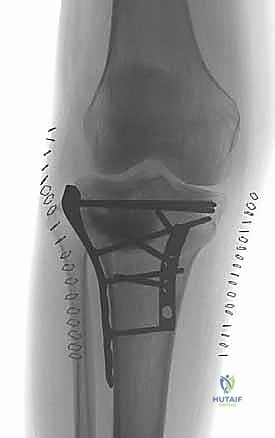

2. التثبيت الداخلي المفتوح (ORIF - Open Reduction and Internal Fixation)

هي العملية النهائية الحاسمة. تتضمن فتح الركبة، إعادة ترتيب الشظايا العظمية كقطع "البازل"، وتثبيتها باستخدام شرائح معدنية تشريحية ومسامير.

2. الشقوق الجراحية (النهج المزدوج - Dual Incision Approach)

لأن الكسر يشمل الجانبين الإنسي والوحشي، فإن شقًا جراحيًا واحدًا لا يكفي. يقوم الدكتور هطيف عادة بعمل شقين منفصلين لضمان عدم سلخ مساحة كبيرة من الجلد وتقليل خطر النخر:

* شق أمامي وحشي (Anterolateral Incision): للوصول إلى اللقمة الوحشية (التي تكون غالبًا مفتتة ومنخسفة).

* شق خلفي إنسي (Posteromedial Incision): للوصول إلى اللقمة الإنسية الك